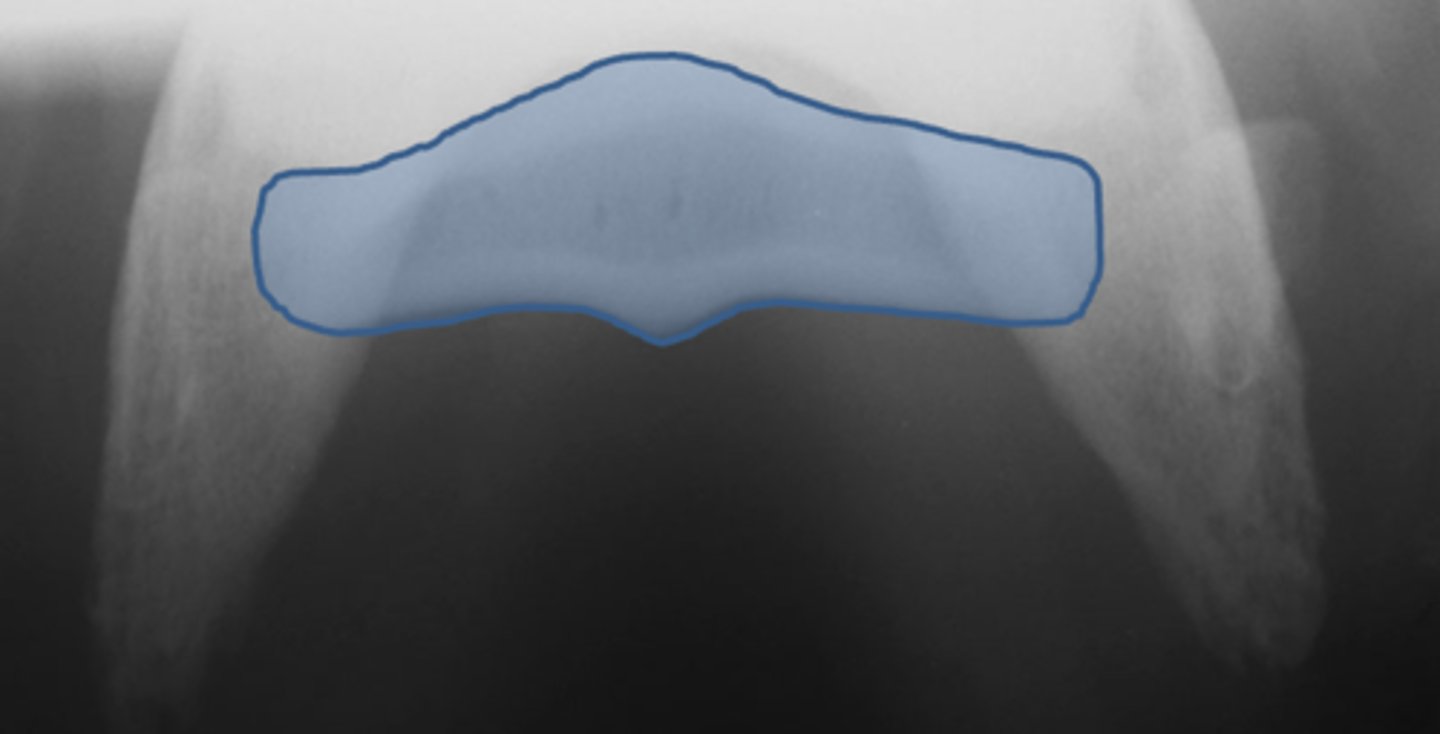

Flexor skyline

What view is this?

1. Flexor surface

2. Corticomedullary distinction

3. Number of synovial invaginations

What is the flexor skyline used to evaluate?